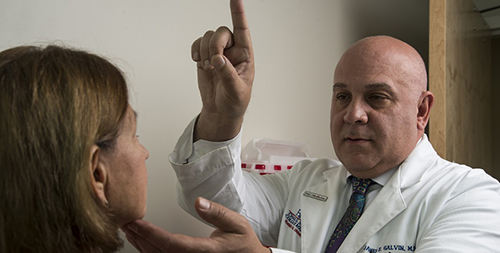

Dr. Jim Galvin, director of FAU's Comprehensive Center for Brain Health (CCBH), received a $3 million, three-year grant from The Harry T. Mangurian, Jr. Foundation to expand the Dementia Prevention Initiative (DPI). This is the second major contribution FAU has received from...

Dr. James Galvin, executive director of FAU's Institute for Healthy Aging and Lifespan Studies (I-HeAL), recently received a $1 million grant from The Harry T. Mangurian, Jr. Foundation to help support his Dementia Prevention Initiative. Dr. Galvin is a world-renowned neuros...